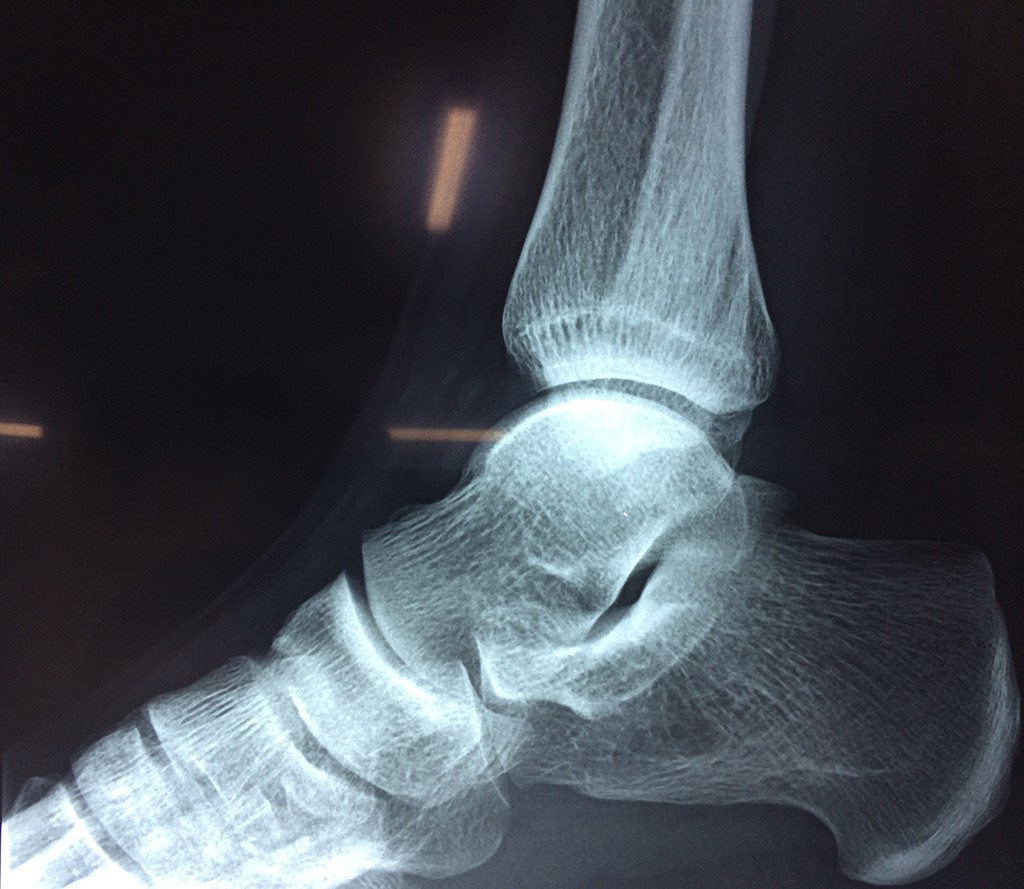

Una fractura de tobillo es la rotura de uno o más de los huesos del tobillo. Estas fracturas pueden ser:

- Parciales (el hueso está sólo parcialmente fisurado, no del todo).

Algunas fracturas de tobillo pueden requerir cirugía si: